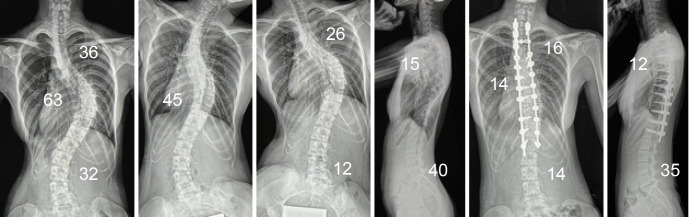

Abstract Image